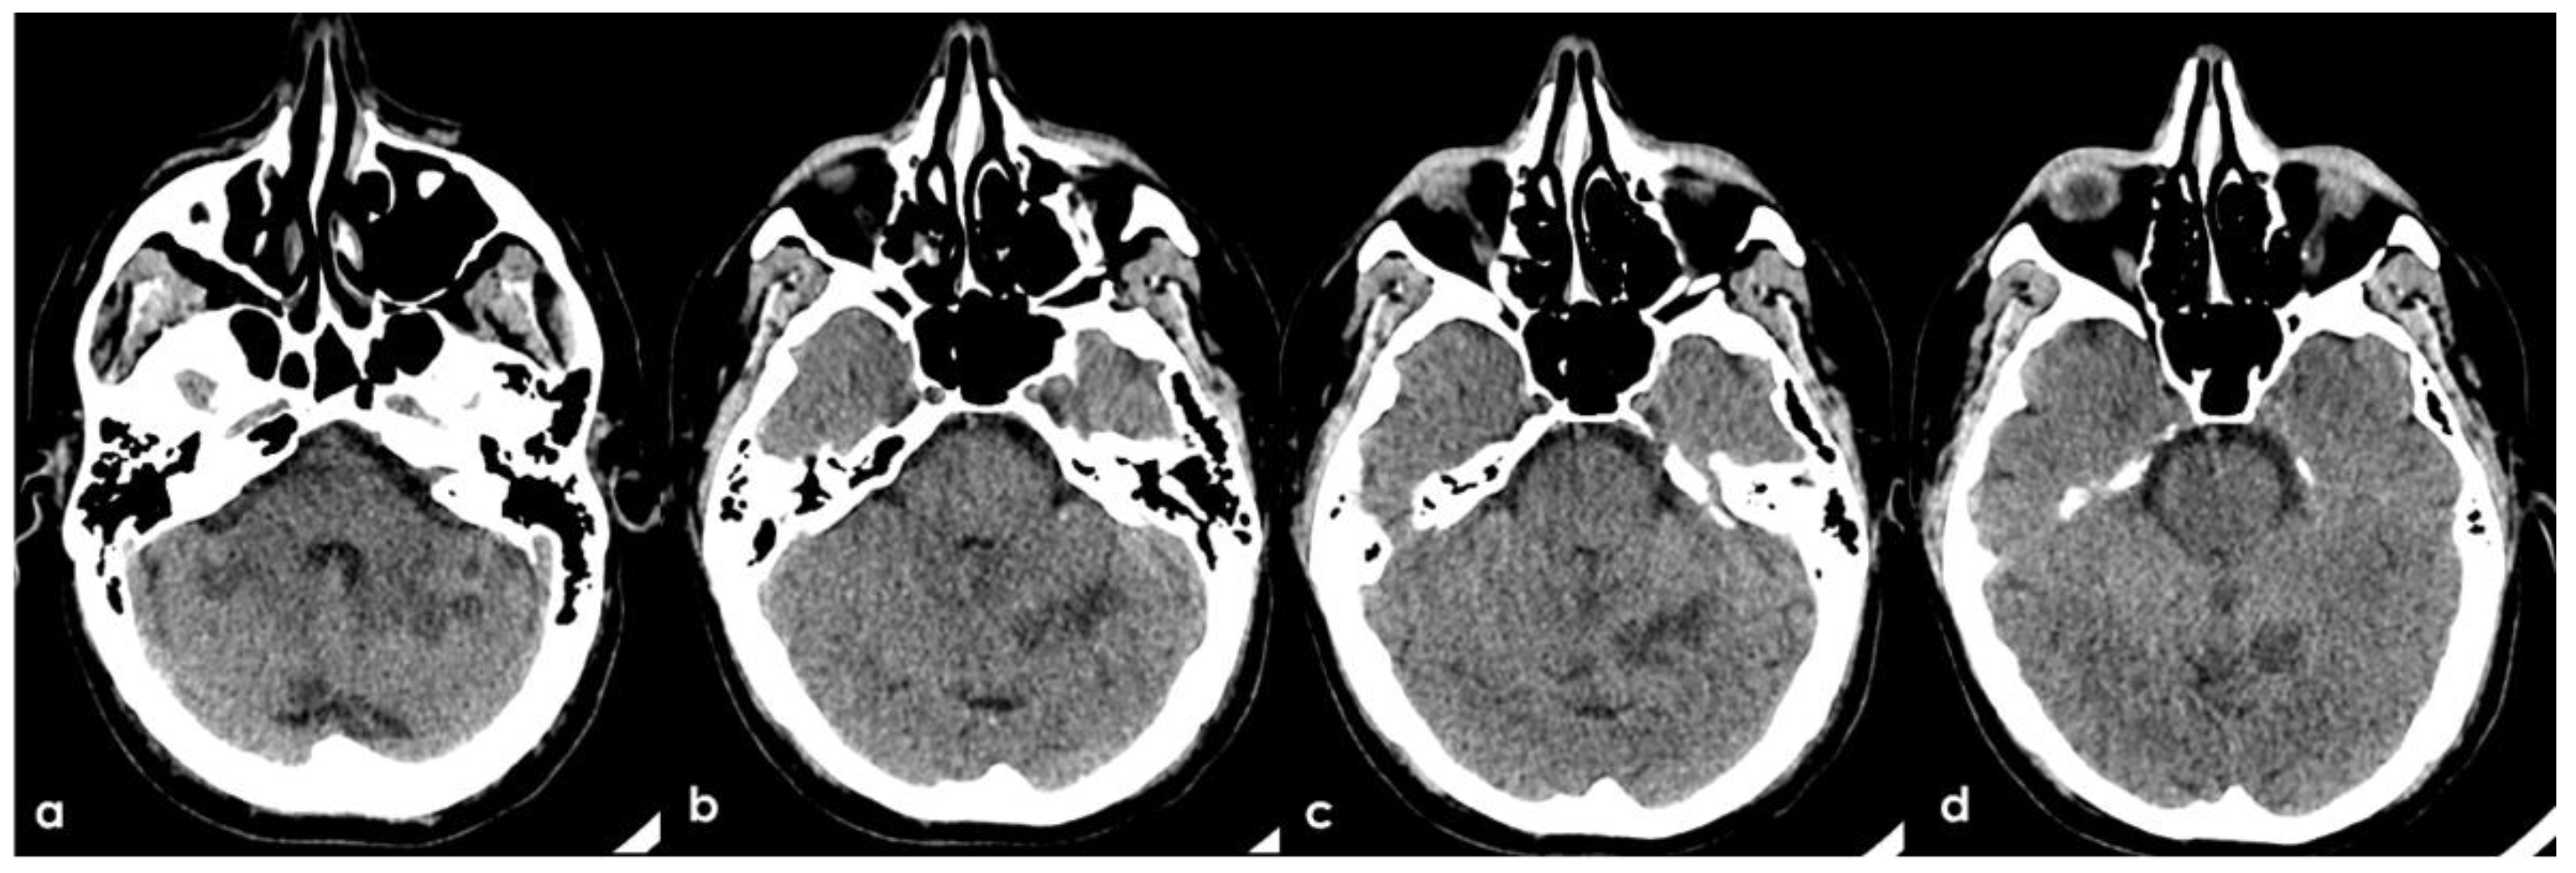

A 46-year-old man was referred to the Emergency Department (ED) in the afternoon because of unsteadiness, vertigo and nausea, reporting the awareness of the symptoms at awakening, around ten hours before the consultation; his last time well was almost 24 h before. His past medical history was notable for two episodes of head concussion without clinical consequences and brain lesions on CT imaging, the recent finding of increased value of glycated hemoglobin and a long-lasting IDA, erratically treated with iron oral supplementation. The first blood laboratory assessment in ED confirmed the microcytic anemia without other relevant findings: hemoglobin 8.3 g/dL (normal range 14.0–17.5 g/dL), RBCs 4.26 × 106/µL (normal range 4.50–6.00 millions/µL), hematocrit 28.6% (normal range 40.0–52.0%), MCV 67.3 fL (normal range 80.0–95.0 fL), MCH 19.5 pg (normal range 26.0–32.0 pg), MCHC 28.9 g/dL (normal range 32.5–36.0 g/dL), platelets 211 × 1000 µL (normal range 150–400 × 1000/µL), fibrinogen 188 mg/dL (normal range 181.0–384.0 mg/dL), D-dimer 2485 ng/mL (normal range 10–500 ng/mL), regular liver and kidney functions, absence of electrolytic disturbances and normal inflammatory markers. The initial neurological examination was remarkable for impaired alertness (psychomotor slowness, tendency to fall asleep), dysarthria and left limbs ataxia with a global National Institute of Health Stroke Scale (NIHSS) score of 11. The patient underwent an unenhanced brain CT scan, whose findings were significant for multiple subcortical hypodensities in both cerebellar hemispheres and vermis, which was highly suggestive of subacute ischemic lesions in the territory of bilateral posterior inferior cerebellar artery (PICA) and left superior cerebellar artery (SCA) (Figure 1).

Figure 1. Brain CT performed at the admittance to the ED. From a to d: ascending axial CT slices of the posterior cranial fossa, showing bilateral subcortical multiple rounded hypodensities in the cerebellar white matter (a) in PICA territory with left side prevalence (b,c) and a similar hyperintense lesion in the superior part of vermis (bd) and in the left anterior lobe of the cerebellum, supplied by the superior cerebellar artery (SCA).